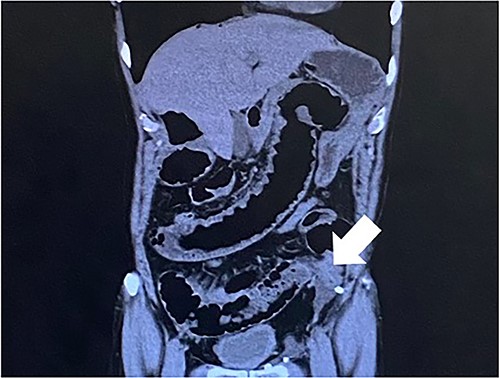

Computed tomography revealed caliber changes in the small bowel at the site of post-hernia repair in the left inguinal region (Figs 1 and 2), and the patient underwent laparoscopic surgery under general anesthesia. Intraperitoneal observation revealed that the peritoneal suture in the left inguinal region was detached, and a hole in the peritoneum had formed a hernial orifice (Fig. 4), causing SBO because of preperitoneal herniation (Fig. 3). The hernia was released, the peritoneal hole was sutured again and the surgery was completed. The postoperative course was good, and the patient was discharged from the hospital on the third postoperative day after reoperation.

The closed peritoneum was lacerated, and the small bowel was incarcerated in the preperitoneal space.